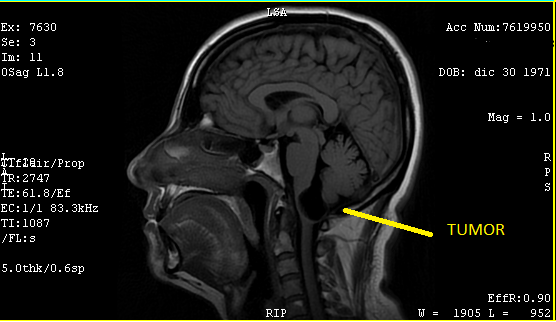

Dos días después, por recomendación y presión, conseguí una cita urgente con un neurocirujano del mismo hospital. Un hombre de mediana edad, de semblante relajado y afable pero de pocas palabras, me recibió y me preguntó cortante por qué había acudido con él. Le conté del ortopedista y le mostré los estudios. Lo confirmo y agregó: "Por la posición donde está alojado el tumor, junto al cerebelo, muy cerca del cuarto ventrículo, es peligroso ya que es de gran tamaño y está bloqueando el paso de líquido cefalorraquídeo a la columna". Obvio no entendí nada de lo que dijo en ese momento, sus palabras no tenían ningún significado para mí, pero por la expresión de su rostro entendí que era algo serio.

El 13 de agosto de 2019, ya con la resonancia de cráneo y los papeles del seguro, acudí con el doctor. Después de verlos me confirmó: "Es un tumor (quiste) benigno con el que nació. Se desconoce por qué se forman, pero una teoría es que son residuos de placenta que se quedan cuando se forma el producto en el vientre. Eso no es un tema, mi principal preocupación es su ubicación y tamaño mide: 3.3cm x 2.1cm x 1.7cm y se comunica con el cuarto ventrículo, y está obstruyendo el paso de líquido cefalorraquídeo a la columna". Me advirtió: "Va a ser un procedimiento muy doloroso, así que debes de estar consciente de ello". Llenó los papeles del seguro con carácter de urgente, con el diagnóstico: Tumor de comportamiento incierto o desconocido en el encéfalo y del sistema nervioso central.

Le pregunte qué: ¿si era un quiste o un tumor?, porque me dijo que es un quiste, pero él en los papeles lo asentó como tumor, me dijo "ambos son correctos, ya que un tumor cerebral es una masa o un crecimiento de células anormales en el cerebro, y existen más de 250 tipos diferentes de tumores cerebrales. Algunos tumores cerebrales son no cancerosos (benignos) y otros, cancerosos (malignos)". Regresando al mío que afortunadamente era benigno, llamó mi atención la manera en que el doctor acercaba y alejaba la imagen en su monitor con el mouse, repitiendo: "Mire, mire, ¿ya vio? El tumor está muy grande, ¿ya lo vio? Mire, mire". Obvio yo no estaba viendo el monitor, lo veía a él y sus reacciones; me limité a contestar: "Sí, doctor, ya lo sé, ya lo vi", pero él seguía fascinado y no le importó mi respuesta, estaba absorto en la imagen e incluso me atrevería a decir que parecía emocionado, ya que no paraba de decir que la ubicación del tumor era algo inusual.